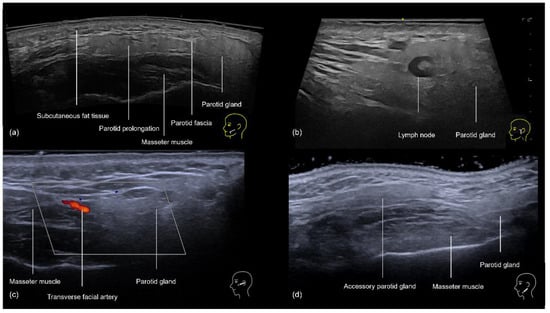

3.4. Zygomatic and Preauricular Region

3.4.1. Sonographic Anatomy of the Zygomatic and Preauricular Region

3.4.2. Ultrasound-Guided Filling Techniques of the Zygomatic and Preauricular Region

- Preauricular Region